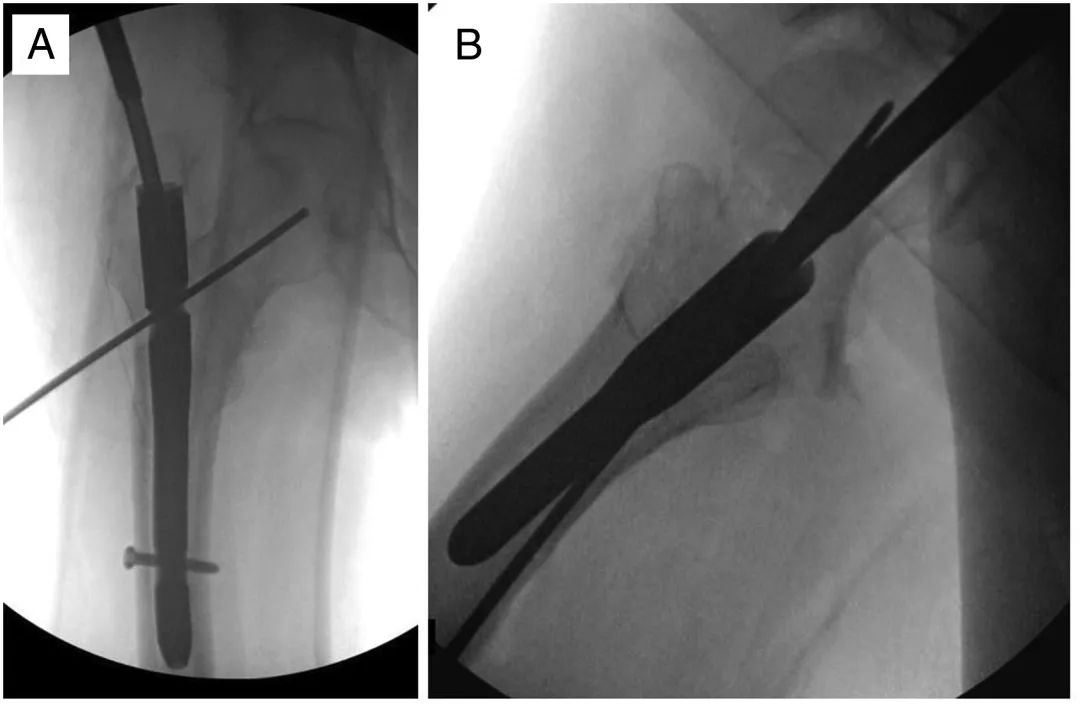

Une nouvelle vis ou lame hélicoïdale est ensuite placée dans l'os sous-chondral de la tête fémorale dans l'axe du col fémoral en veillant à ne pas pénétrer dans la tête (Figure 4).La vis est placée intentionnellement en évitant le trajet de l'ongle précédent, mais toujours pointée vers le centre de la tête fémorale.(Figure 5)

Figure 4, images antéropostérieures (A) et latérales (B) d'un autre patient montrant l'insertion de l'aiguille à rainurer le long du trajet du nouveau clou de tête.